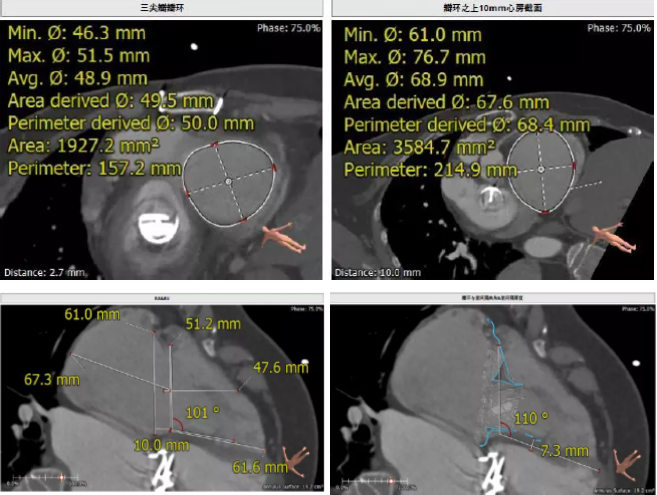

患者64歲女性,18年前接受了“正中開胸二尖瓣機(jī)械瓣置換術(shù)”,2年前超聲檢查發(fā)現(xiàn)“三尖瓣重度返流”。輾轉(zhuǎn)多地,嘗試各種治療方式,均無明顯改善。由于存在相關(guān)合并癥,傳統(tǒng)外科手術(shù)風(fēng)險大,郭惠明教授團(tuán)隊(duì)結(jié)合該患者CT、超聲檢查結(jié)果,對該患者的情況進(jìn)行了充分的評估和討論,決定采用LuX-Valve人工三尖瓣介入瓣膜置換系統(tǒng)對患者進(jìn)行微創(chuàng)介入治療,以最小的創(chuàng)傷解決患者的病痛。

術(shù)前CT評估